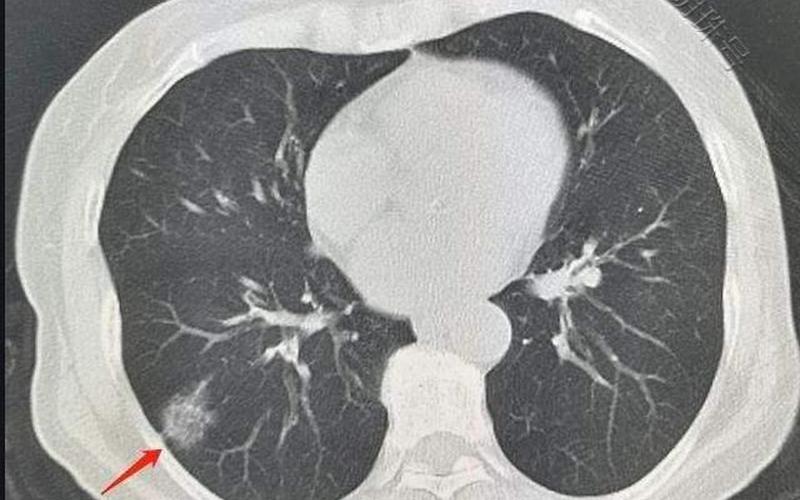

北京科兴肺结节是一种针对肺结节的检测服务,由北京科兴生物制品有限公司推出。该服务主要通过基因检测技术,对肺结节进行分析,以判断其是否为恶性肿瘤。该服务的推出,旨在帮助人们更早地发现肺癌,从而提高治疗的成功率。

基因检测技术是一种通过检测人体细胞的基因序列,来判断是否存在某种疾病的技术。在肺结节检测中,基因检测技术可以通过分析肺结节细胞的基因序列,来判断其是否为恶性肿瘤。

北京科兴肺结节的检测流程主要包括样本采集、DNA提取、PCR扩增、测序、数据分析等步骤。其中,样本采集可以通过肺活检、经皮穿刺等方式进行。在DNA提取过程中,可以采用化学 *** 或者机械 *** 。PCR扩增是指通过聚合酶链反应,将DNA复制成数百万份。测序是指通过测序仪对DNA进行测序。通过数据分析,可以得到肺结节是否为恶性肿瘤的判断结果。